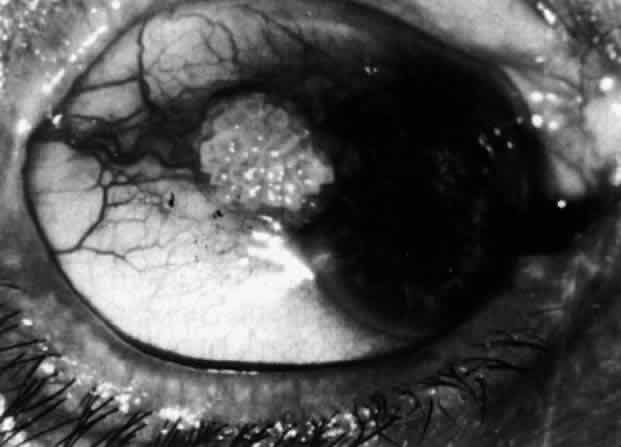

Simple and nodular episcleritis differ in their clinical courses, but in both the edema and infiltration are entirely within the episcleral tissues. The sclera is not involved. The maximum congestion is in the superficial episcleral network, with some slight congestion of the conjunctival vessels and deep episcleral vessels (Fig. 10). The intraocular structures are not involved in either variety, nor is the visual acuity affected. Anterior segment fluorescein angiography reveals a normal vascular pattern but a very rapid flow rate, with the whole transit of the dye being completed within 2 or 3 seconds (Figs. 11 and 12).

Fig. 11. Anterior segment fluorescein angiogram of a 45-year-old woman with simple episcleritis. At first transit of dye, all the vessels are dilated and filling simultaneously. However, the vascular pattern is not disturbed.

Fig. 12. Angiogram of the same 45-year-old woman in Figure 11 one second later. Within 1 second, all the vessels are filled and there is even, venular filling except in the deep episcleral plexus. This is the rapid filling pattern seen in all forms of episcleritis and in diffuse anterior scleritis.